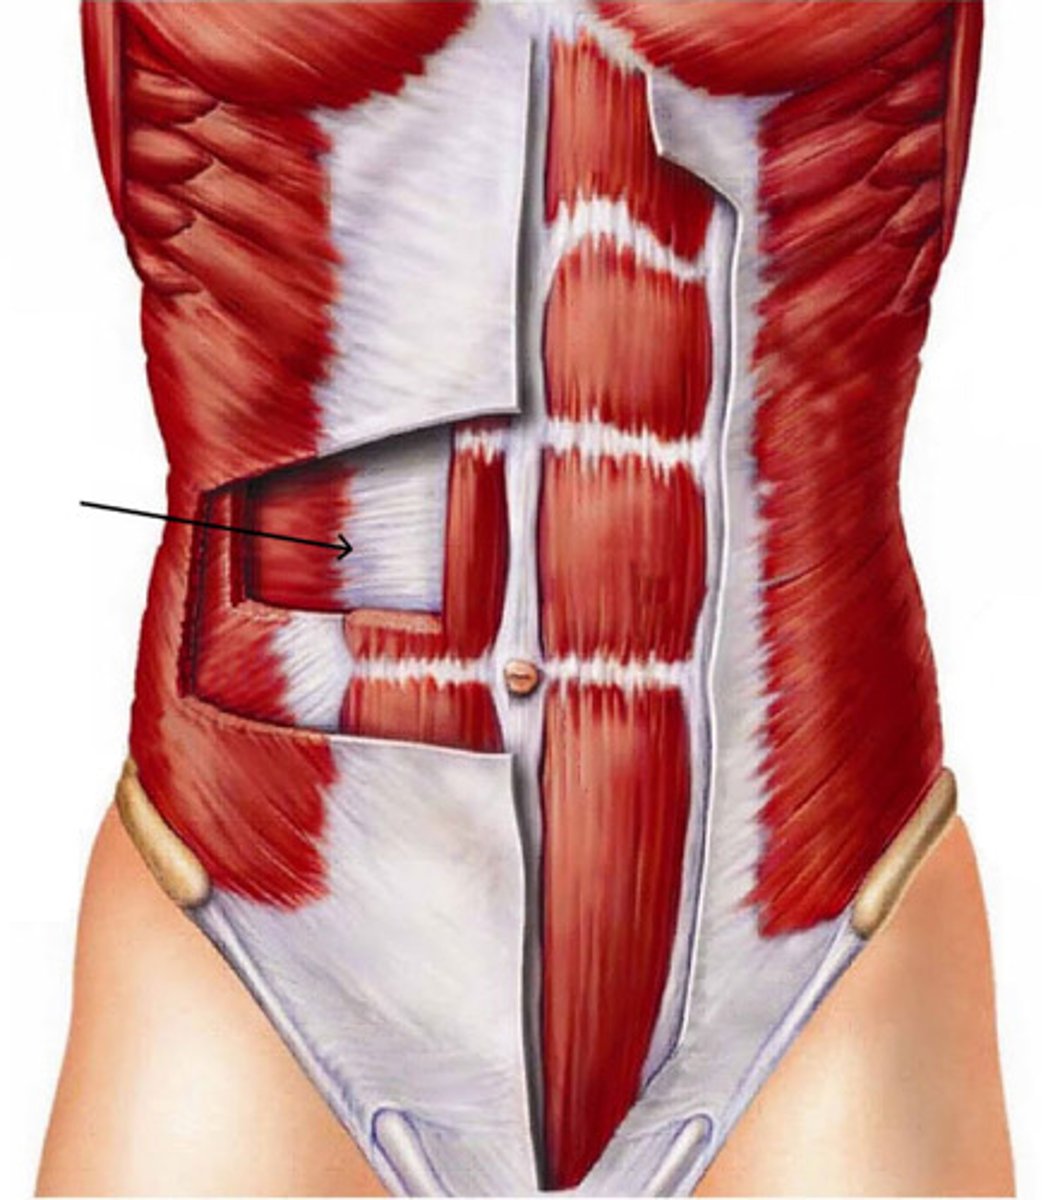

external oblique

internal oblique

transversus abdominus

rectus abdominus

tendinous insertions

Aponeurosis

rectus sheath